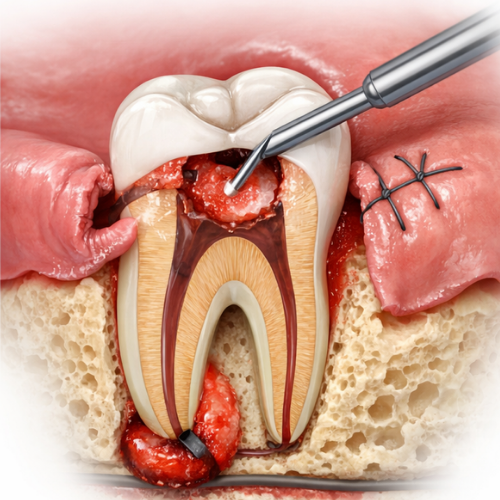

Surgical root canal treatment is needed only in a few cases. It is advised when the infection cannot be fully removed through the normal root canal method. This may happen if the infection is present at the tip of the root or if the tooth has a complex root structure. In this procedure, a small opening is made in the gum near the root to clean the infected area and help the tooth heal properly.

Surgical Root Canal

Surgical Root Canal Treatment